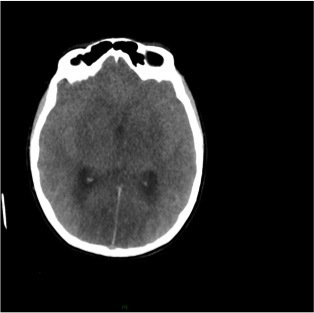

Un scanner cérébral sans injection est réalisé. Les reformations axiales vous sont présentées.

Question 10 : Ce scanner présente :

Les espaces sous sous-arachnoidiens ne sont plus visibles. Ne pas confondre la substance grise qui arrive au contact des os du crâne, avec une hyperdensité spontanée méningée.

Le volume des ventricules paraît faussement augmenté du fait de l’effacement diffus des sillons corticaux.

Qui traduit une augmentation du volume cérébral.

Aucun des deux hémisphères cérébraux ne passe sous la faux du cerveau. L’augmentation du volume cérébral est diffuse.

Effacement diffus des sillons corticaux avec début de dédifférenciation des de la substance blanche - substance grise notamment des noyaux centraux. Cela traduit un œdème cérébral diffus secondaire à un bas débit cérébral.